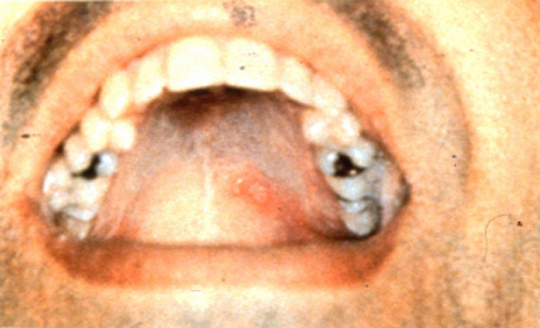

Hand, foot and mouth disease

Ulcerated lesion on hard palate